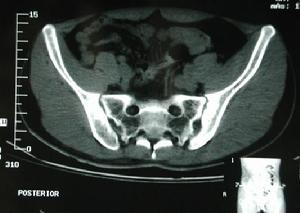

3.影像學檢查所見 主要是在X線平片上顯示退變徵視病程不同而出現退行性變的各期表現,以增生及骨刺為主。

X線片上主要顯示退變徵,視病程不同而出現退行變的各期表現,以增生骨刺為主。